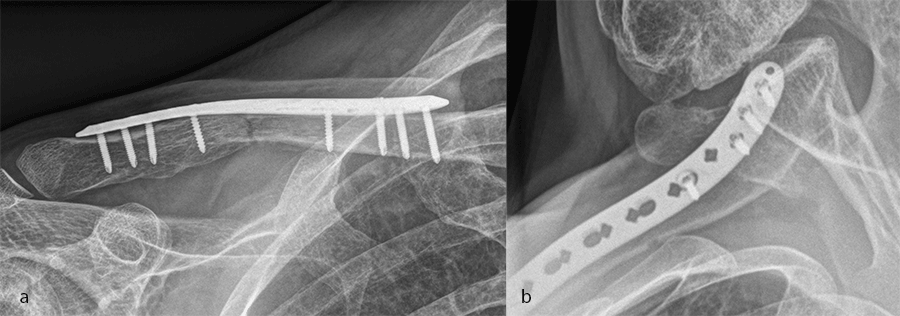

A 30-year-old man sustained a lateral fracture to his left clavicle following a fall from his bike (Fig 9). Intraoperative images indicate plate placement and screw insertion (Fig 10). Intraoperative image revealing usage of sutures through the plate for soft- tissue fixation (Fig 11). Image shows the fracture healing at 8 weeks' follow-up (Fig 12).